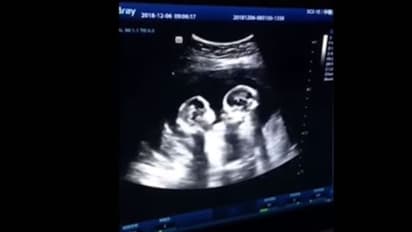

സഹോദരങ്ങള് തമ്മിലുള്ള ഈ 'ശത്രുത' ഗര്ഭപാത്രത്തില് നിന്നേ തുടങ്ങുന്നുവെന്നാണ് ഇപ്പോള് വൈറലായിക്കൊണ്ടിരിക്കുന്ന ഒരു വീഡിയോ തെളിയിക്കുന്നത്. അമ്മയുടെ ഗര്ഭപാത്രത്തില് കിടക്കുന്ന ഇരട്ടക്കുഞ്ഞുങ്ങള് തമ്മില് അടികൂടുന്നതിന്റെ സ്കാനിംഗ് ദൃശ്യങ്ങളാണ് കയ്യടികളേറ്റുവാങ്ങി സമൂഹമാധ്യമങ്ങളില് ഓടിക്കൊണ്ടിരിക്കുന്നത്.

ചൈനയിലെ യിന്ചുവാനിലുള്ള ആശുപത്രിയില് കഴിഞ്ഞ ഡിസംബറില് നടന്ന സ്കാനിംഗിന്റെ ദൃശ്യങ്ങളാണ് ഇപ്പോള് പുറത്തുവന്നിരിക്കുന്നത്. യുവതിയുടെ ഭര്ത്താവാണ് സ്കാനിംഗ് മോണിട്ടറില് കണ്ട അത്യപൂര്വ്വമായ ദൃശ്യങ്ങള് ഷൂട്ട് ചെയ്ത് പുറത്തുവിട്ടത്.

കുഞ്ഞുങ്ങള് മുഖാമുഖം കിടന്ന് രണ്ട് മുതിര്ന്ന ആളുകളെ പോലെ വഴക്ക് കൂടുന്നതാണ് ദൃശ്യങ്ങളിലുള്ളത്. ജനുവരിയില് വീണ്ടും സ്കാനിംഗ് നടത്തിയപ്പോള് സീന് ആകെ മാറി. രണ്ടുപേരും പരസ്പരം കെട്ടിപ്പിടിച്ച് സ്നേഹമായിരിക്കുന്നു. എന്താായാലും ഏപ്രില് എട്ടോടെ, അല്പസ്വല്പം പ്രശ്നങ്ങളെല്ലാം സൃഷ്ടിച്ച്, സിസേറിയനിലൂടെ ഇരട്ട പെണ്കുഞ്ഞുങ്ങള് പുറത്തുവന്നു.